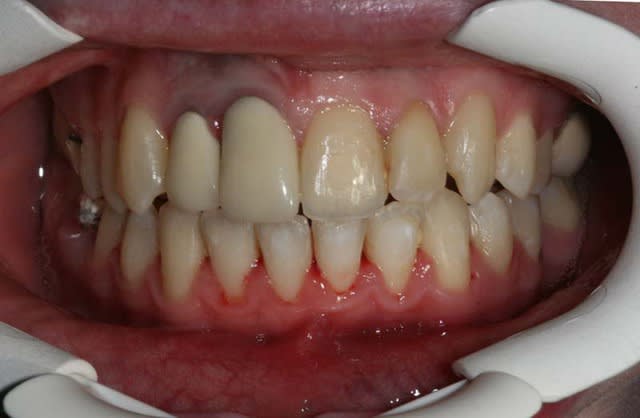

Voici le cas il y a 8 jours, c.a.d. 1 an et 1 mois après les photos de son dernier rendez vous

entre temps, elle est allée se faire faire des provisoires sur 12/11 par un confrère plus prés de son domicile

voici le résultat de l’absence de contention, qui aurait été (a mon avis) une erreur compte tenu que le cas n’était pas terminé

c’est mal foutu, c’est déglingué mais je n’ai aucune malposition Inc. Inf.

c.a.d. : AUCUNE RECIDIVE D’ENCOMBREMENT AVEC ROTATIONS

les dents ne sont pas alignées, mais j’ai mon espace globale, je peux poursuivre ce traitement avec sérénité

elle n’est pas défigurée,

elle n’a pas de migraines

pas d’acouphènes

pas de DAM.

etc ...

A votre avis pourquoi ?